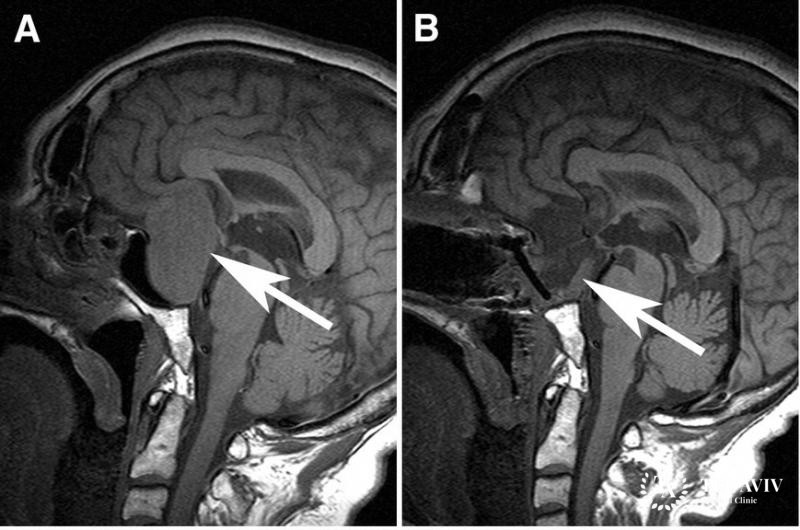

- МРТ или КТ;